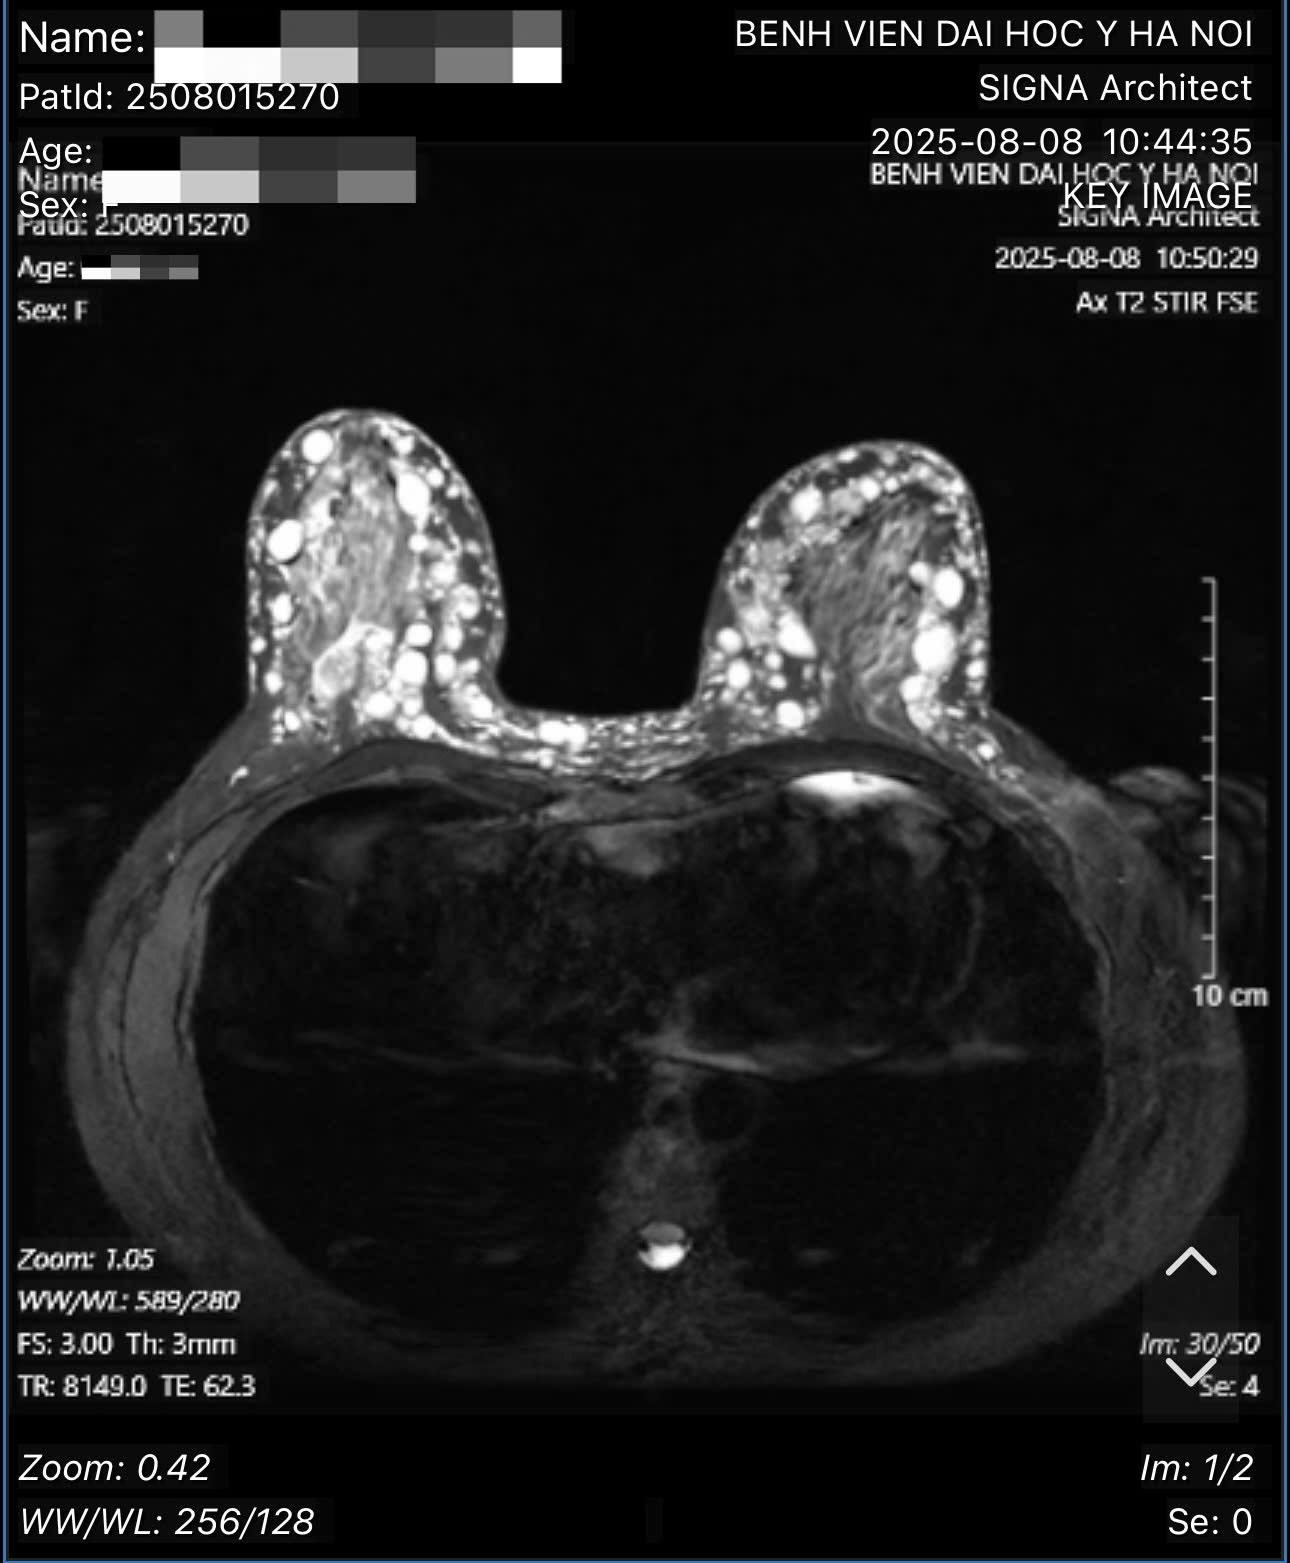

Ảnh chụp cắt lớp cho thấy tình trạng diễn tiến u hạt silicon hai bên ngực.

Theo bác sĩ Hồng, qua thăm khám, xét nghiệm và các hình ảnh chụp chiếu, bác sĩ xác định bệnh nhân bị u hạt silicon hai bên ngực (hay còn gọi là siliconoma), thâm nhiễm toàn bộ tổ chức tuyến vú hai bên, đến các tổ chức mỡ dưới da, trung bì da, hay sâu đến lớp cân cơ ngực lớn, là biến chứng của việc tiêm silicon lỏng. Bên cạnh đó, bệnh nhân cũng từng tiêm silicon ở vùng má và đùi, đều đã xuất hiện các cục siliconoma ở vùng má và chân. Tuy nhiên, ở hai bên ngực, các tổn thương đã tiến triển gây biến chứng, các u hạt silicon lan rất sát tới vùng da, cần giải quyết trước. Nếu để lâu hơn, các hạt này tiếp tục đẩy ra sẽ dẫn đến nguy cơ nhiễm trùng, thậm chí hoại tử da vùng ngực.